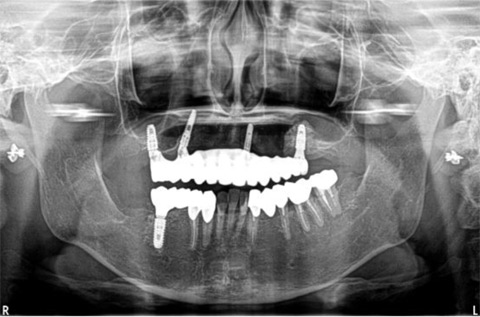

上顎、下顎のいずれか1列分の歯を、4本のインプラント体で固定する治療についての症例です。

施行名 : 審美歯科(虫歯などをインプラント体によって改善する施術)